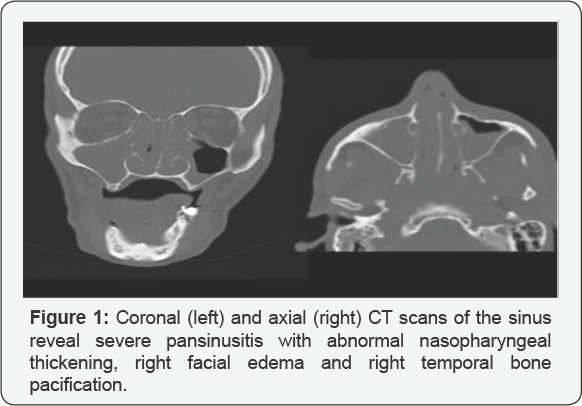

Midline destructive lesions of the face were first described in 1897, and later a variety of terms were proposed. Angiocentric lymphoma, malignant granuloma, malignant midline reticulosis, and polymorphic reticulosis. Previously known as lethal midline granuloma or STEWART granuloma, was first introduced in the large category of granulomatous diseases like Wegener, because of the histopathology-chronic inflammatory granulomatous destructive process, but a lots of chronic infections like Tuberculosis, Leprosis, Mucormycosis, and tumors have a similar aspect, but the treatment implicate chimio, radiotherapy after all other possibilities were excluded. This tumor is responsible for the classical destruction of the mid face. In the past, death resulted from inter-current infection of disseminated lymphoma due to a failure of diagnosis or insufficiently. Aggressive oncologic treatment. Recently, similar appearances of aggressive mid facial destruction caused by Cocaine abuse have been reported in which tests for granulomatous diseases and lymphoma have been negative. Todays mid facial necrotizing disease is a naso facial natural killer (NK)/T-cell lymphoma, characterized by granulomatous lesion with destruction of the upper aero digestive tract. Naso facial definitively categorized in the World Health Organization lymphoma classification system as nasal type extra-nodal NK/T-cell lymphoma. It is common in Asian origin whereas rare in western population. It is difficult to diagnose because of the wide array of similar pathology and nonspecific symptoms. It occurs around the 4th decade and male to female ratio is 8:1 to 2:1. Common sites for sinonasal NK/T-cell lymphomas are: nasal cavities the maxillary sinus, nasopharynx, or pharynx, tonsils palate, oral cavity, and hypo pharynx Figure 1.

In the same time I order cultures for fungi like Aspergillus, Candidiasis, Mucor. Also I run a battery of blood test to appreciate the general status of the patient others for the differential diagnosis, in fact in that time it was an excluding diagnosis with. Wegener granulomatosis=PANCA, CANCA, biopsy histopathology, IHC Tuberculosis-RX thorax, ex BK direct, cultures, Protein chain reaction, Quanti FERON test Tertiary syphilis guma RBW, VDRL , biopsy histopathology, IHC Leprosy biopsy,B. Hansae, cultures Rhinoscleroma Klebsiella rhinos cleromatis, biopsy histopathology ,IHC Cancers biopsy histopathology, IHC Mucormicosis cultures, biopsy histopathology, IHCCT, MRI scans axial, coronal view revealed pansinusitis, necrosis of the intersinuso nasal wall destruction of the inf turbinate perforation of the nasal septum, the extension of the process also endocranial extension. Finally we send the patient on TG .MURES on Oncological Clinic , where my diagnosis was confirm They report the case and it was the single patient with Lethal Midline Granuloma in Europe. They use an aggressive protocol of chemo-radiotherapy but without response .He return without the nasal pyramid, with the hole in his mid face, with high fever, fetid nasal discharge [21-25].